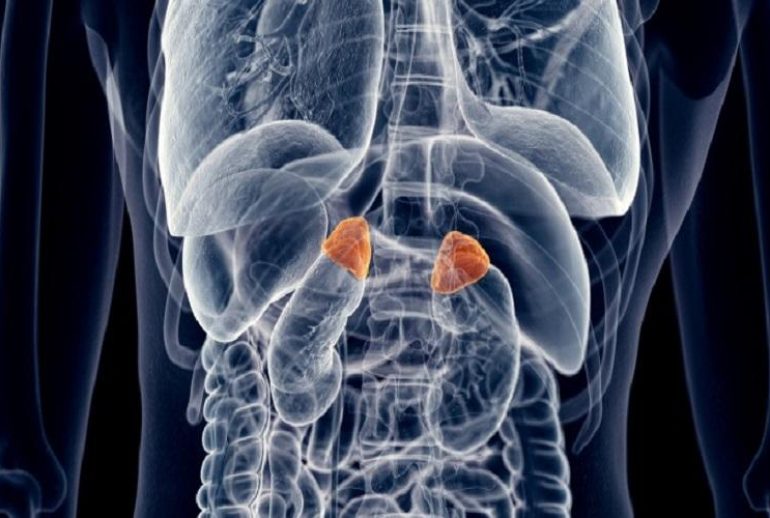

هیپرپلازی مادرزادی آدرنال (CAH) یکی از اختلالات نادر غدد درونریز است که از بدو تولد وجود دارد. این بیماری بر عملکرد غدد فوق کلیوی تأثیر میگذارد و میتواند عوارض جدی برای سلامتی فرد ایجاد کند. در این مقاله، به بررسی جامع این بیماری، علائم، علل، روشهای تشخیص و درمان آن میپردازیم.

این اختلال ژنتیکی باعث میشود غدد فوق کلیوی نتوانند به اندازه کافی کورتیزول و در برخی موارد آلدوسترون تولید کنند. در نتیجه، بدن برای جبران این کمبود، تولید هورمون محرک آدرنوکورتیکوتروپیک (ACTH) را افزایش میدهد که منجر به تولید بیش از حد آندروژنها (هورمونهای مردانه) میشود.